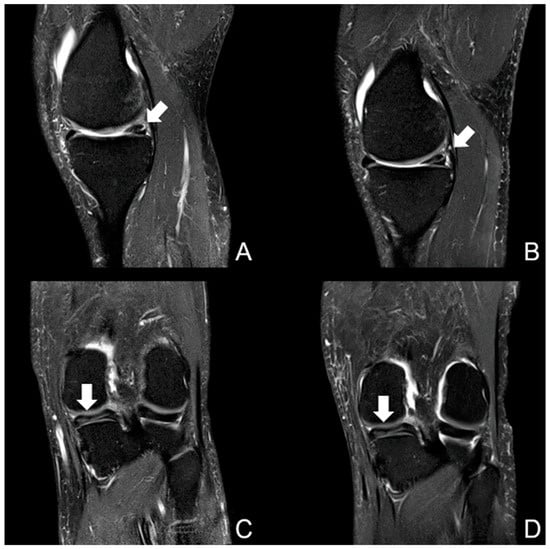

3.2. Visibility of Anatomical Structures and Detected Pathologies